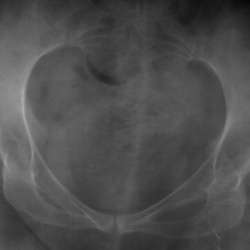

Коллеги, здравствуйте!  Женщина, 65. Первоначально снимали поясничный отдел. Глаз зацепился за кольцевидную тень за крестцом, досняли таз. Та же тень, только анфас в левой подвздошной кости...